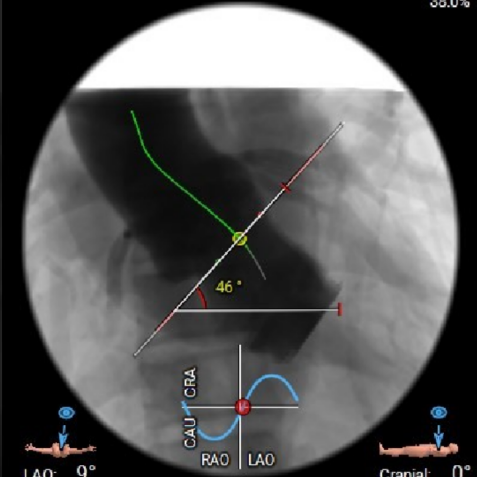

● 主动脉瓣环水平夹角46度,非横位心,主动脉弓角度宽度尚可;

虚拟瓣环与水平夹角

图片

术前考虑右侧股动脉为主入路,左侧为辅助入路。非横位心,主动脉弓角度、宽度尚可,预估输送器过弓难度适宜,跨瓣难度适宜,术中必要时采用Snare辅助。左右冠脉开口高度可,左冠切线角度测量瓣叶大于LCA开口下缘到根部距离,结合瓦氏窦及STJ尺寸预估,冠脉风险适中,建议术中密切关注左冠灌注情况。外周入路走行适宜,腹主中下端和左右髂总散在钙化,血管内径尚可,血管内壁存在不规则纤维增厚和钙化斑,入路穿刺规范操作,小心通过,避免入路血管损伤及相关并发症。重度钙化二叶式病变重度主动脉瓣狭窄,其瓣口面积小,瓣口限制明显,术中瓣膜锚定难度较大,瓣膜植入受二叶瓣瓣叶及团块状钙化挤压存在移位及少量偏多瓣周漏风险,为避免手术并发症,手术预装AV26瓣膜,根据20mm球囊预扩结果选择瓣膜型号,计划瓣膜瓣上3mm开始释放。